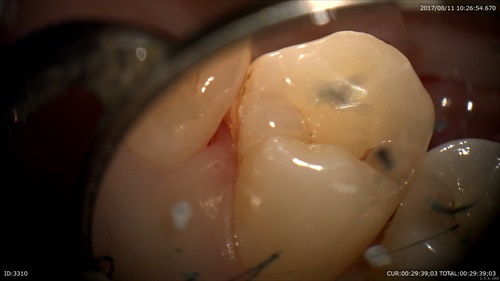

綺麗になりました。

そしてレーザー

一緒に画像をみながら笑って治療していました。歯ブラシを頑張っていただけるので歯周病がどんどん良くなりますね!充実した午前中でした。明日からのお盆休みに向け午後の診療もがんばりますーー。当院は18日までお休みを頂きます。